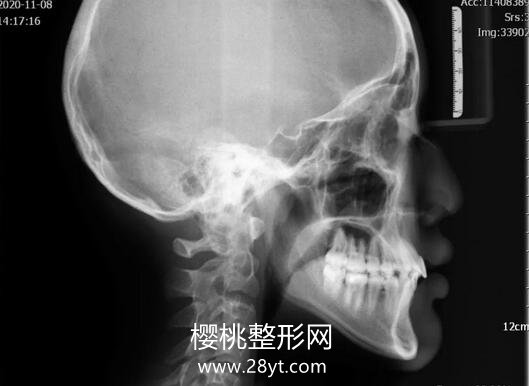

侧面观 直面型,鼻唇角正常,上唇位于E线后1mm,下唇位于E线后2mm。 口内检查 前牙Ⅱ度深覆,覆盖正常,左侧尖牙磨牙关系远中尖尖,右侧磨牙关系远中尖尖,上颌Ⅱ度拥挤,下颌Ⅰ度拥挤,上中线左偏1mm,下中线基本正常,spee曲较深。53乳牙滞留,22舌侧位,个别牙反。

治疗前CBCT所示关节图像诊断 安氏II类,毛氏I1+II2+IV1,III类骨面型,均角治疗计划 采用MBT直丝弓矫治技术;扩出间隙利用垂直开大曲将22纳入牙弓内,观察咬合变化,若依然磨牙II类则推上磨牙向后;拔除53,自制nance托加牵引钩牵引13埋伏牙,排齐牙列,建立正常咬合关系。治疗结果 成功牵引出埋伏牙;个别牙反纠正;覆盖正常;尖牙磨牙关系中性;中线正。

治疗前后头影测量结果对比矫治体会安氏Ⅱ类要分析病因,是否有个别牙的阻挡导致下颌后退位置,首先解除咬合锁结,让下颌恢复到稳定的咬合位置后再进行下一步治疗;埋伏牙的牵引,需要拍摄CT观察埋伏牙的方向位置,分析阻力来源,施加牵引力方向要正确,并尽量避开可能碰到其他牙齿,以免造成牙根吸收。